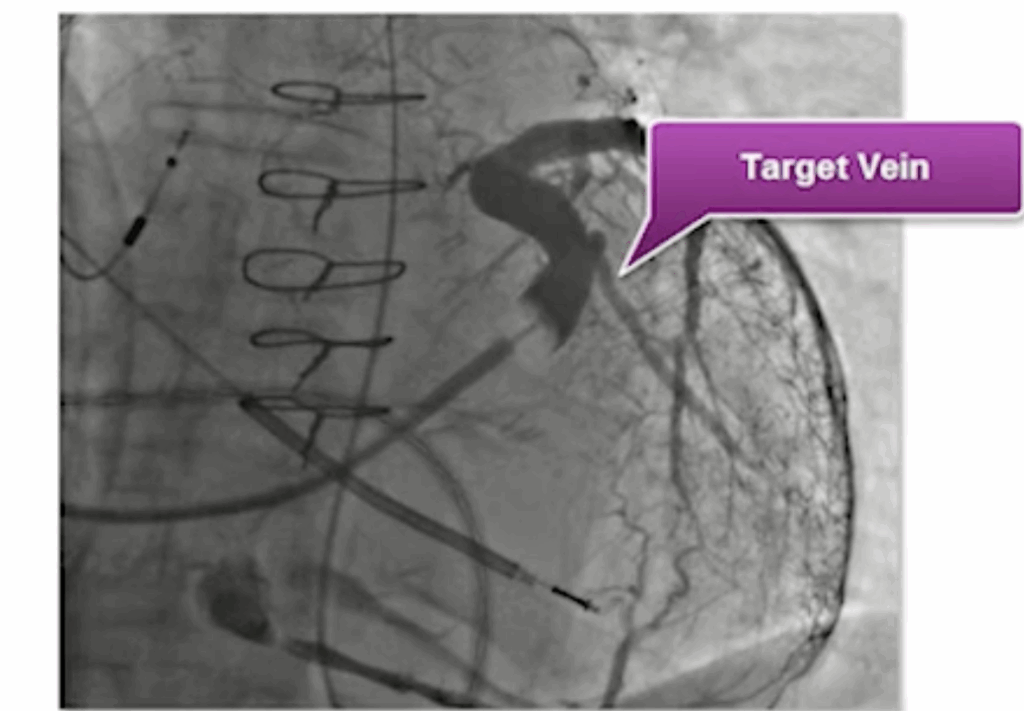

After positioning the RV lead first, the next step is to cannulate the coronary sinus and inject contrast in both LAO and RAO views to identify the optimal target vein for placing the LV lead.

The most effective pacing site is usually mid-lateral on the left ventricular wall.

In order of preference, the veins to target are (veins in the 2-5 o’clock position LAO) :

1. Posterolateral vein

2. Lateral marginal vein

3. Lateral branches of the anterior interventricular vein

These locations typically offer the best electrical delay and the highest likelihood of achieving a favorable CRT response.

Example of target vein (LAO view)